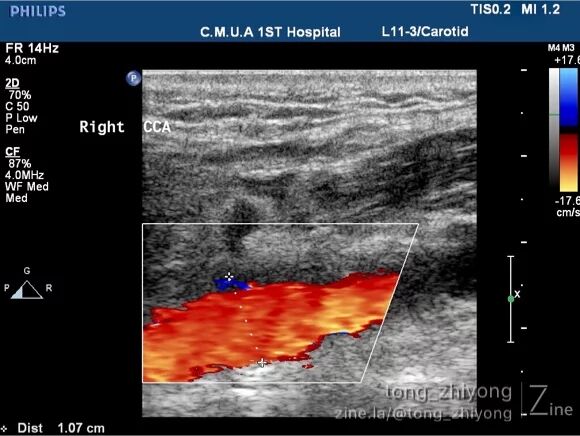

术后一周超声可见:颈总动脉、颈动脉分叉部及颈内动脉近段彩色血流充盈良好,未见明显涡流信号。

术后一周超声可见:颈内动脉近段彩色血流充盈良好,未见涡流。